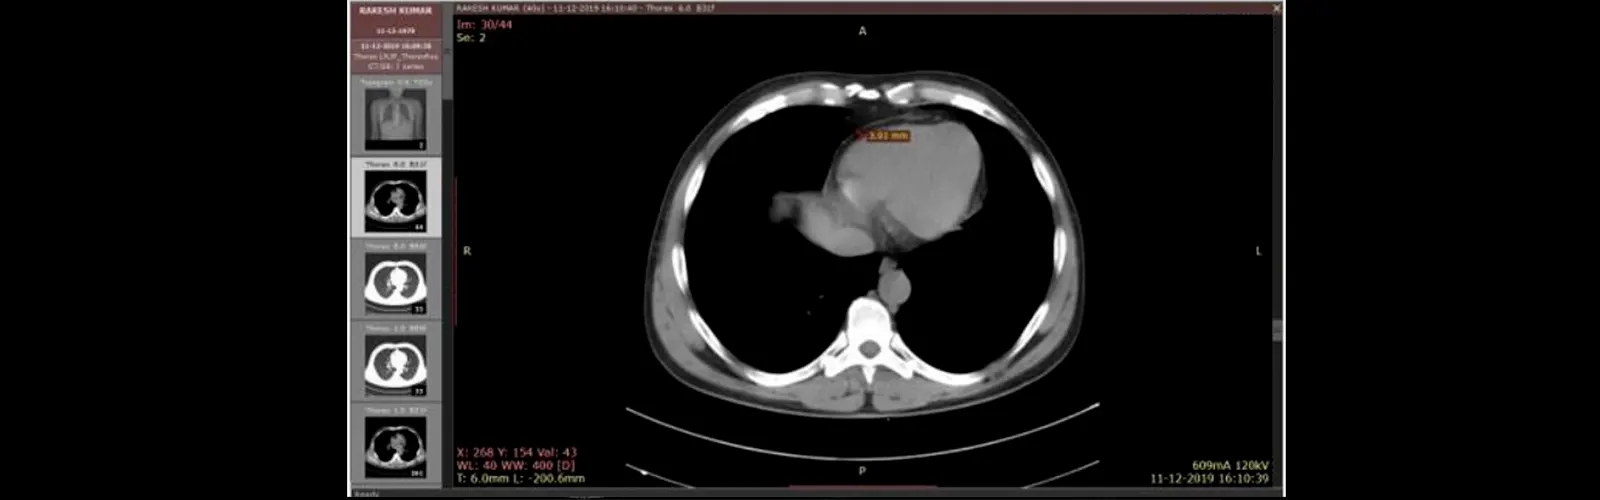

There are many reasons why your doctor recommends you NCCT Chest Scan such as:

Chest Pain: If you experience chest pain, NCCT Chest Scan can help determining if there is damage or abnormalities in the chest that may be causing chest pain.

Respiratory Symptoms: If you experience respiratory symptoms such as coughing, wheezing or shortness of breath, NCCT chest scan can help diagnose underlying health causes.

Lung Cancer: NCCT Chest scan is very useful tool for diagnosing and detecting lung cancer. It can detect lung cancer at an initial stage when the treatment options are more effective.

Pneumonia: NCCT Chest scan can help diagnose pneumonia, a lung infection that can be serious if left untreated.

Pulmonary Embolism: NCCT Chest can help in detecting pulmonary embolism, a condition where blood clots form in the lungs, blocking blood flow and causing chest pain and difficulty breathing.

Chest trauma: If you have experienced chest trauma from an injury or accident, NCCT chest can help evaluate the extent of the damage and guide appropriate treatment.